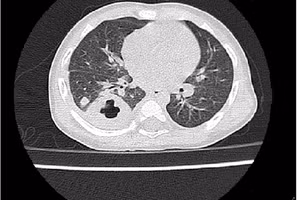

GD&TĐ - Từ một vết xước nhỏ ngoài da khi làm ruộng, người đàn ông 50 tuổi ở Tây Ninh có tiền sử xơ gan bị vi khuẩn "ăn thịt người" tấn công.

GD&TĐ - Nguyên nhân gây bệnh Whitmore (còn gọi là bệnh vi khuẩn ăn thịt người) là do vi khuẩn Burkholderia pseudomallei.